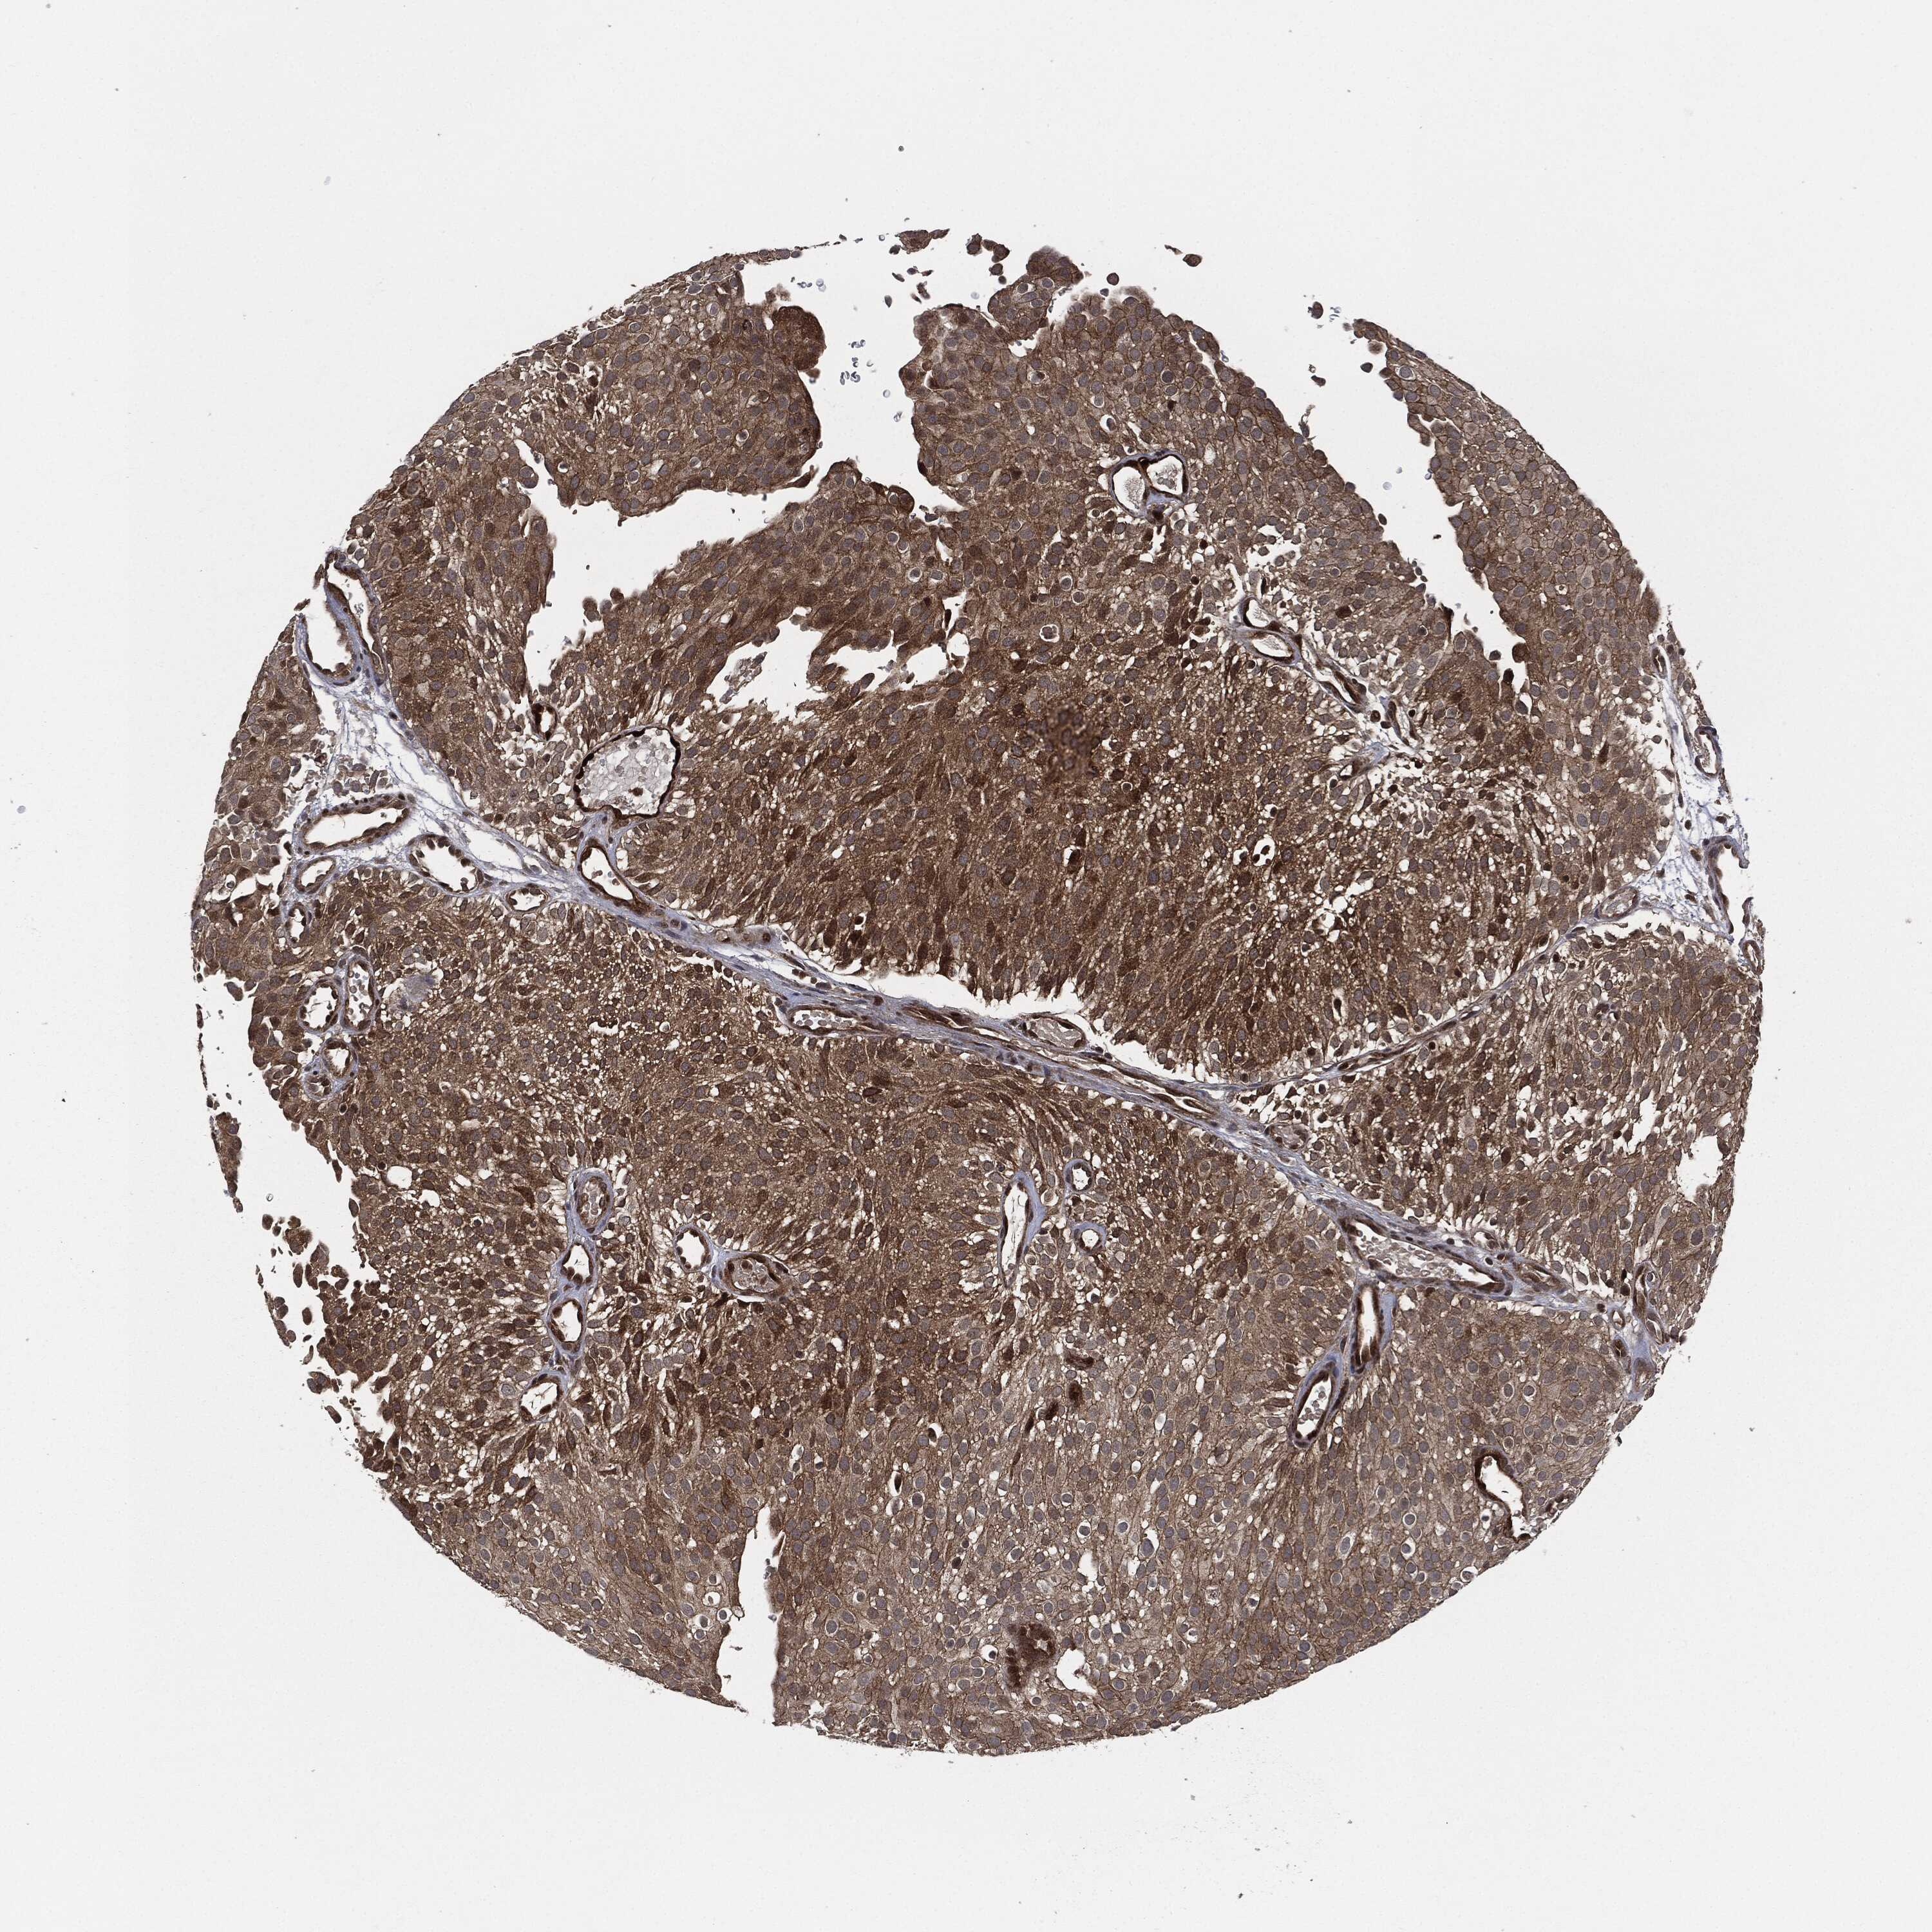

UROTHELIAL CANCER - Protein expressioni

A mouse-over function shows sample information and annotation data. Click on an image to view it in a full screen mode. Samples can be filtered based on level of antibody staining by selecting one or several of the following categories: high, medium, low and not detected. The assay and annotation is described here.

Note that samples used for immunohistochemistry by the Human Protein Atlas do not correspond to samples in the TCGA dataset.

Antibody stainingi

Antibody staining in the annotated cell types in the current human tissue is reported as not detected, low, medium, or high, based on conventional immunohistochemistry profiling in selected tissues. This score is based on the combination of the staining intensity and fraction of stained cells.

Each image is clickable and will lead to virtual microscopy that enables deeper exploration of all samples and also displays staining intensity scores, fraction scores and subcellular localization as well as patient and tissue information for each sample.

CAB002015

Urothelial carcinoma, High grade

Urothelial carcinoma, NOS

Urothelial carcinoma, Low grade

Adenocarcinoma, NOS